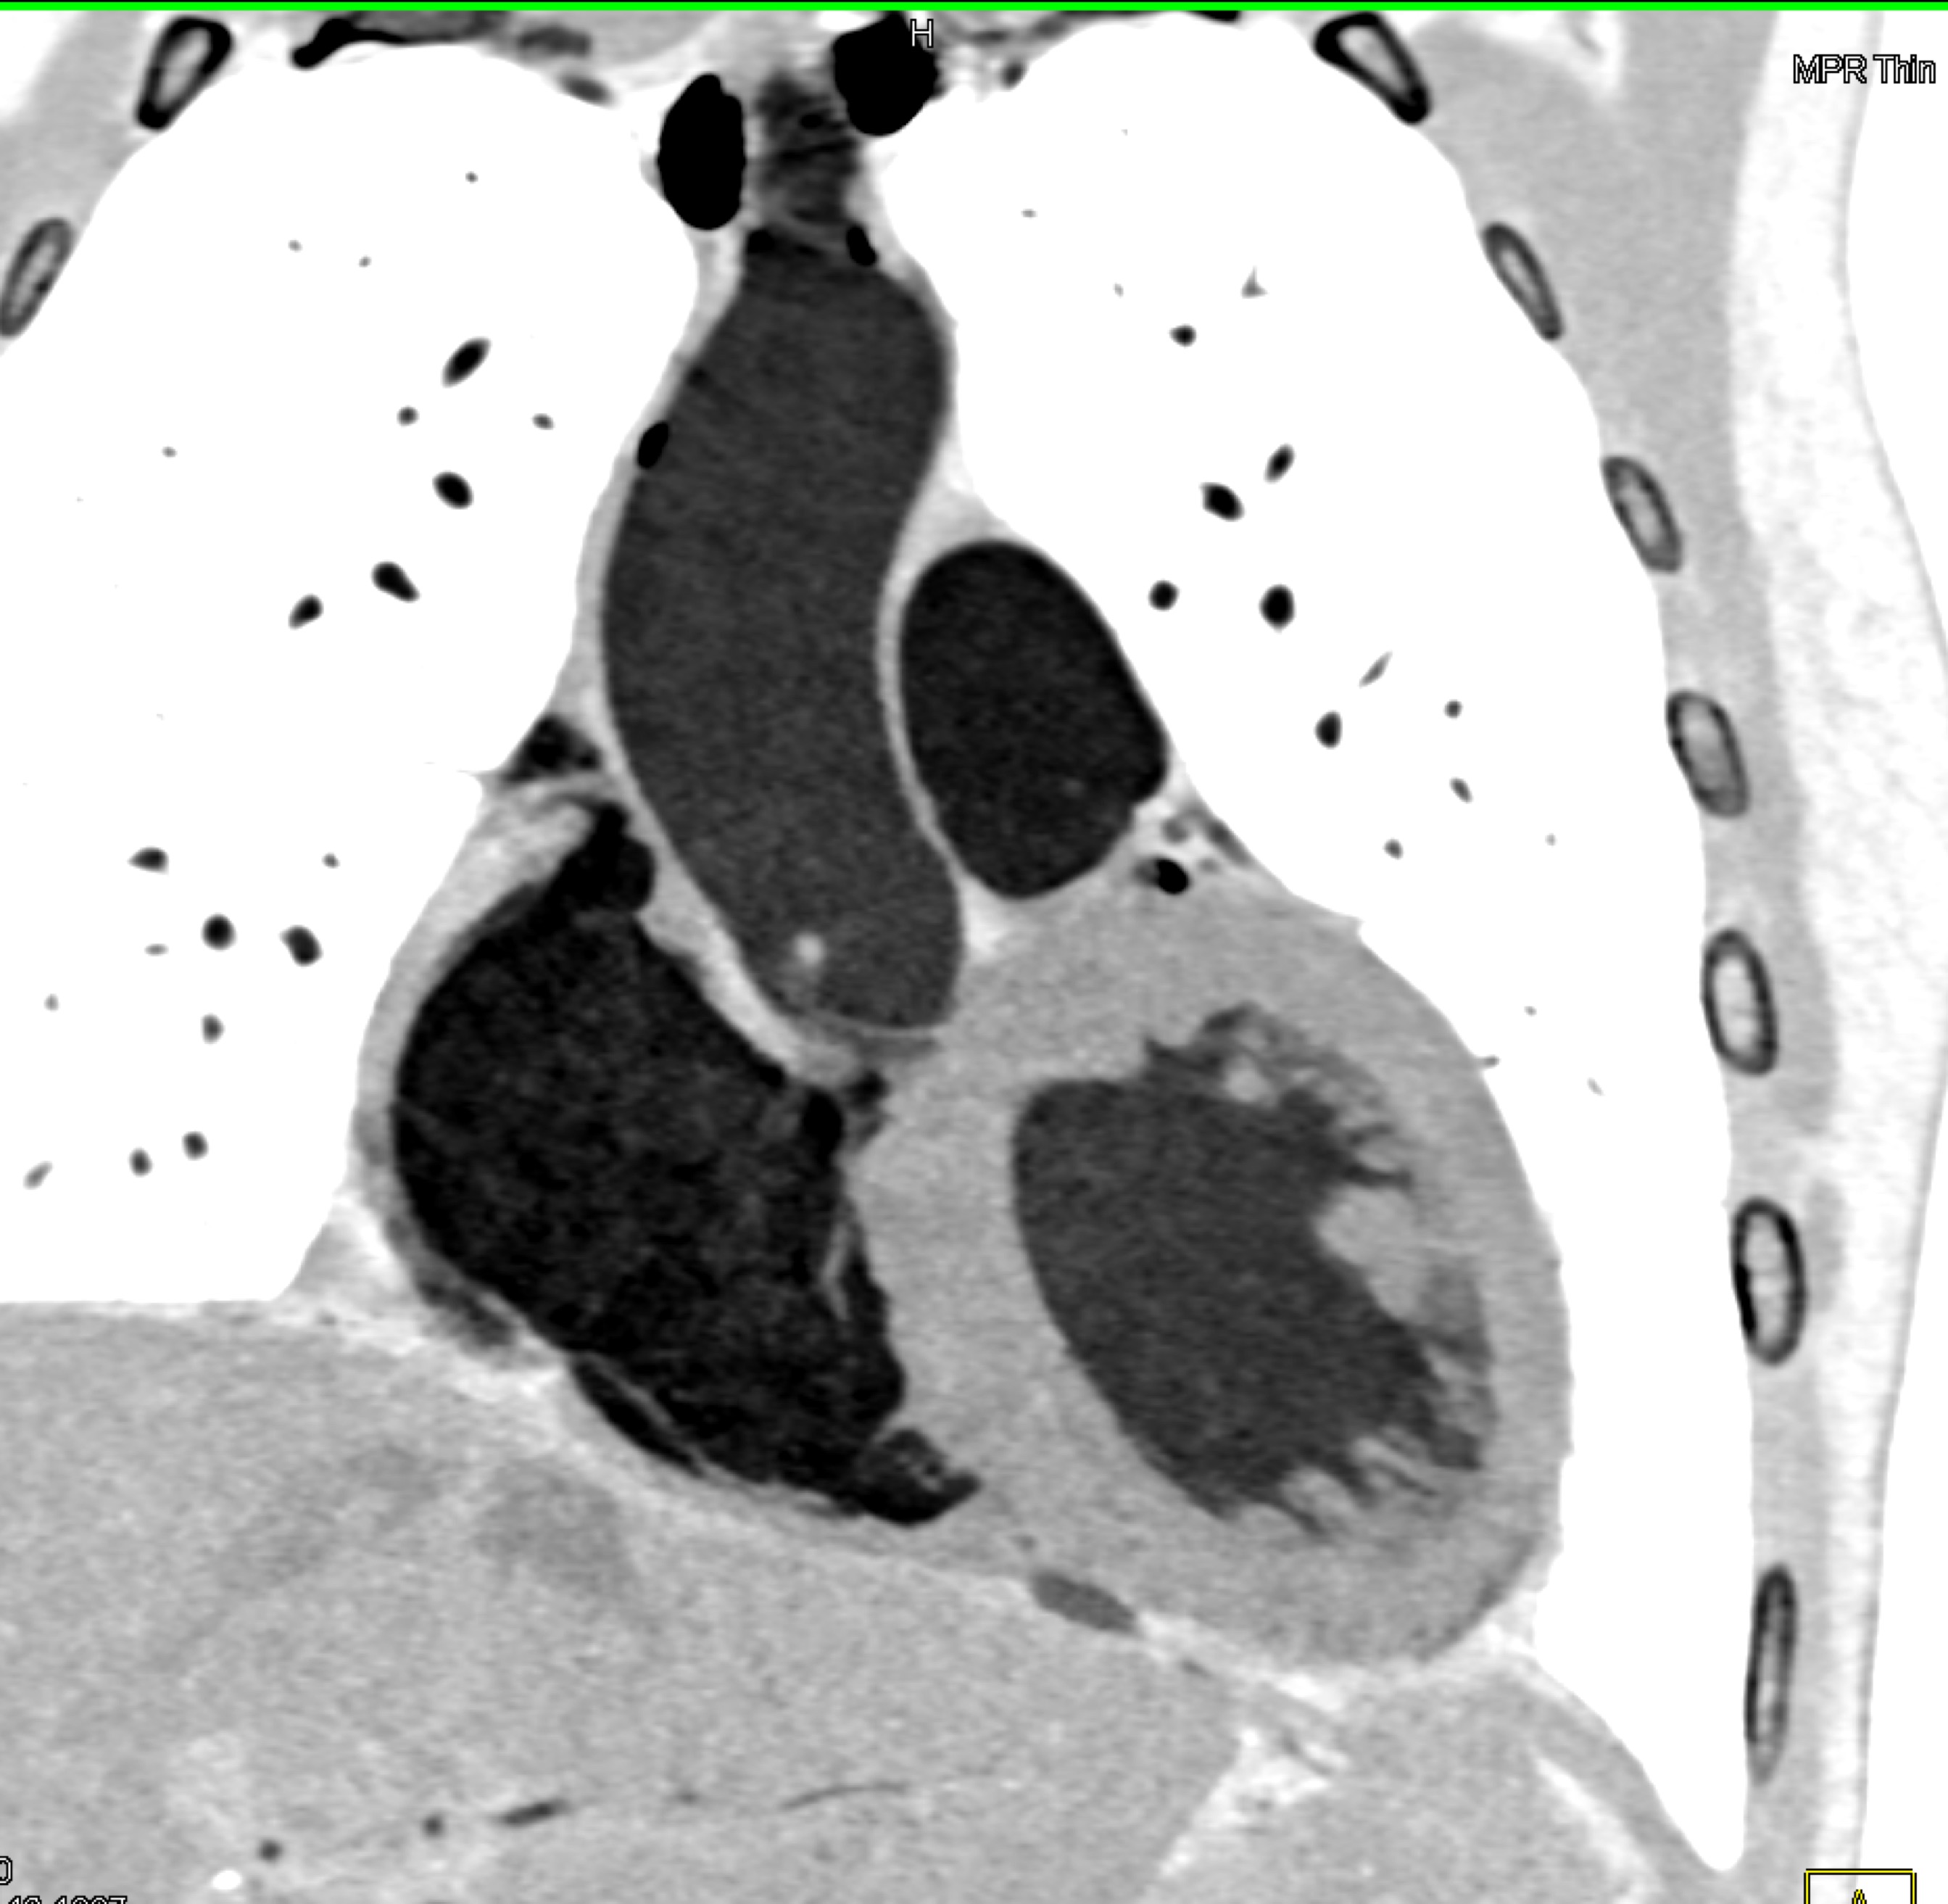

9) The key finding on this coronary CTA in this patient with chest pain is?

LAD occlusion

LAD stenosis

RCA occlusion

RCA arises off the left cusp